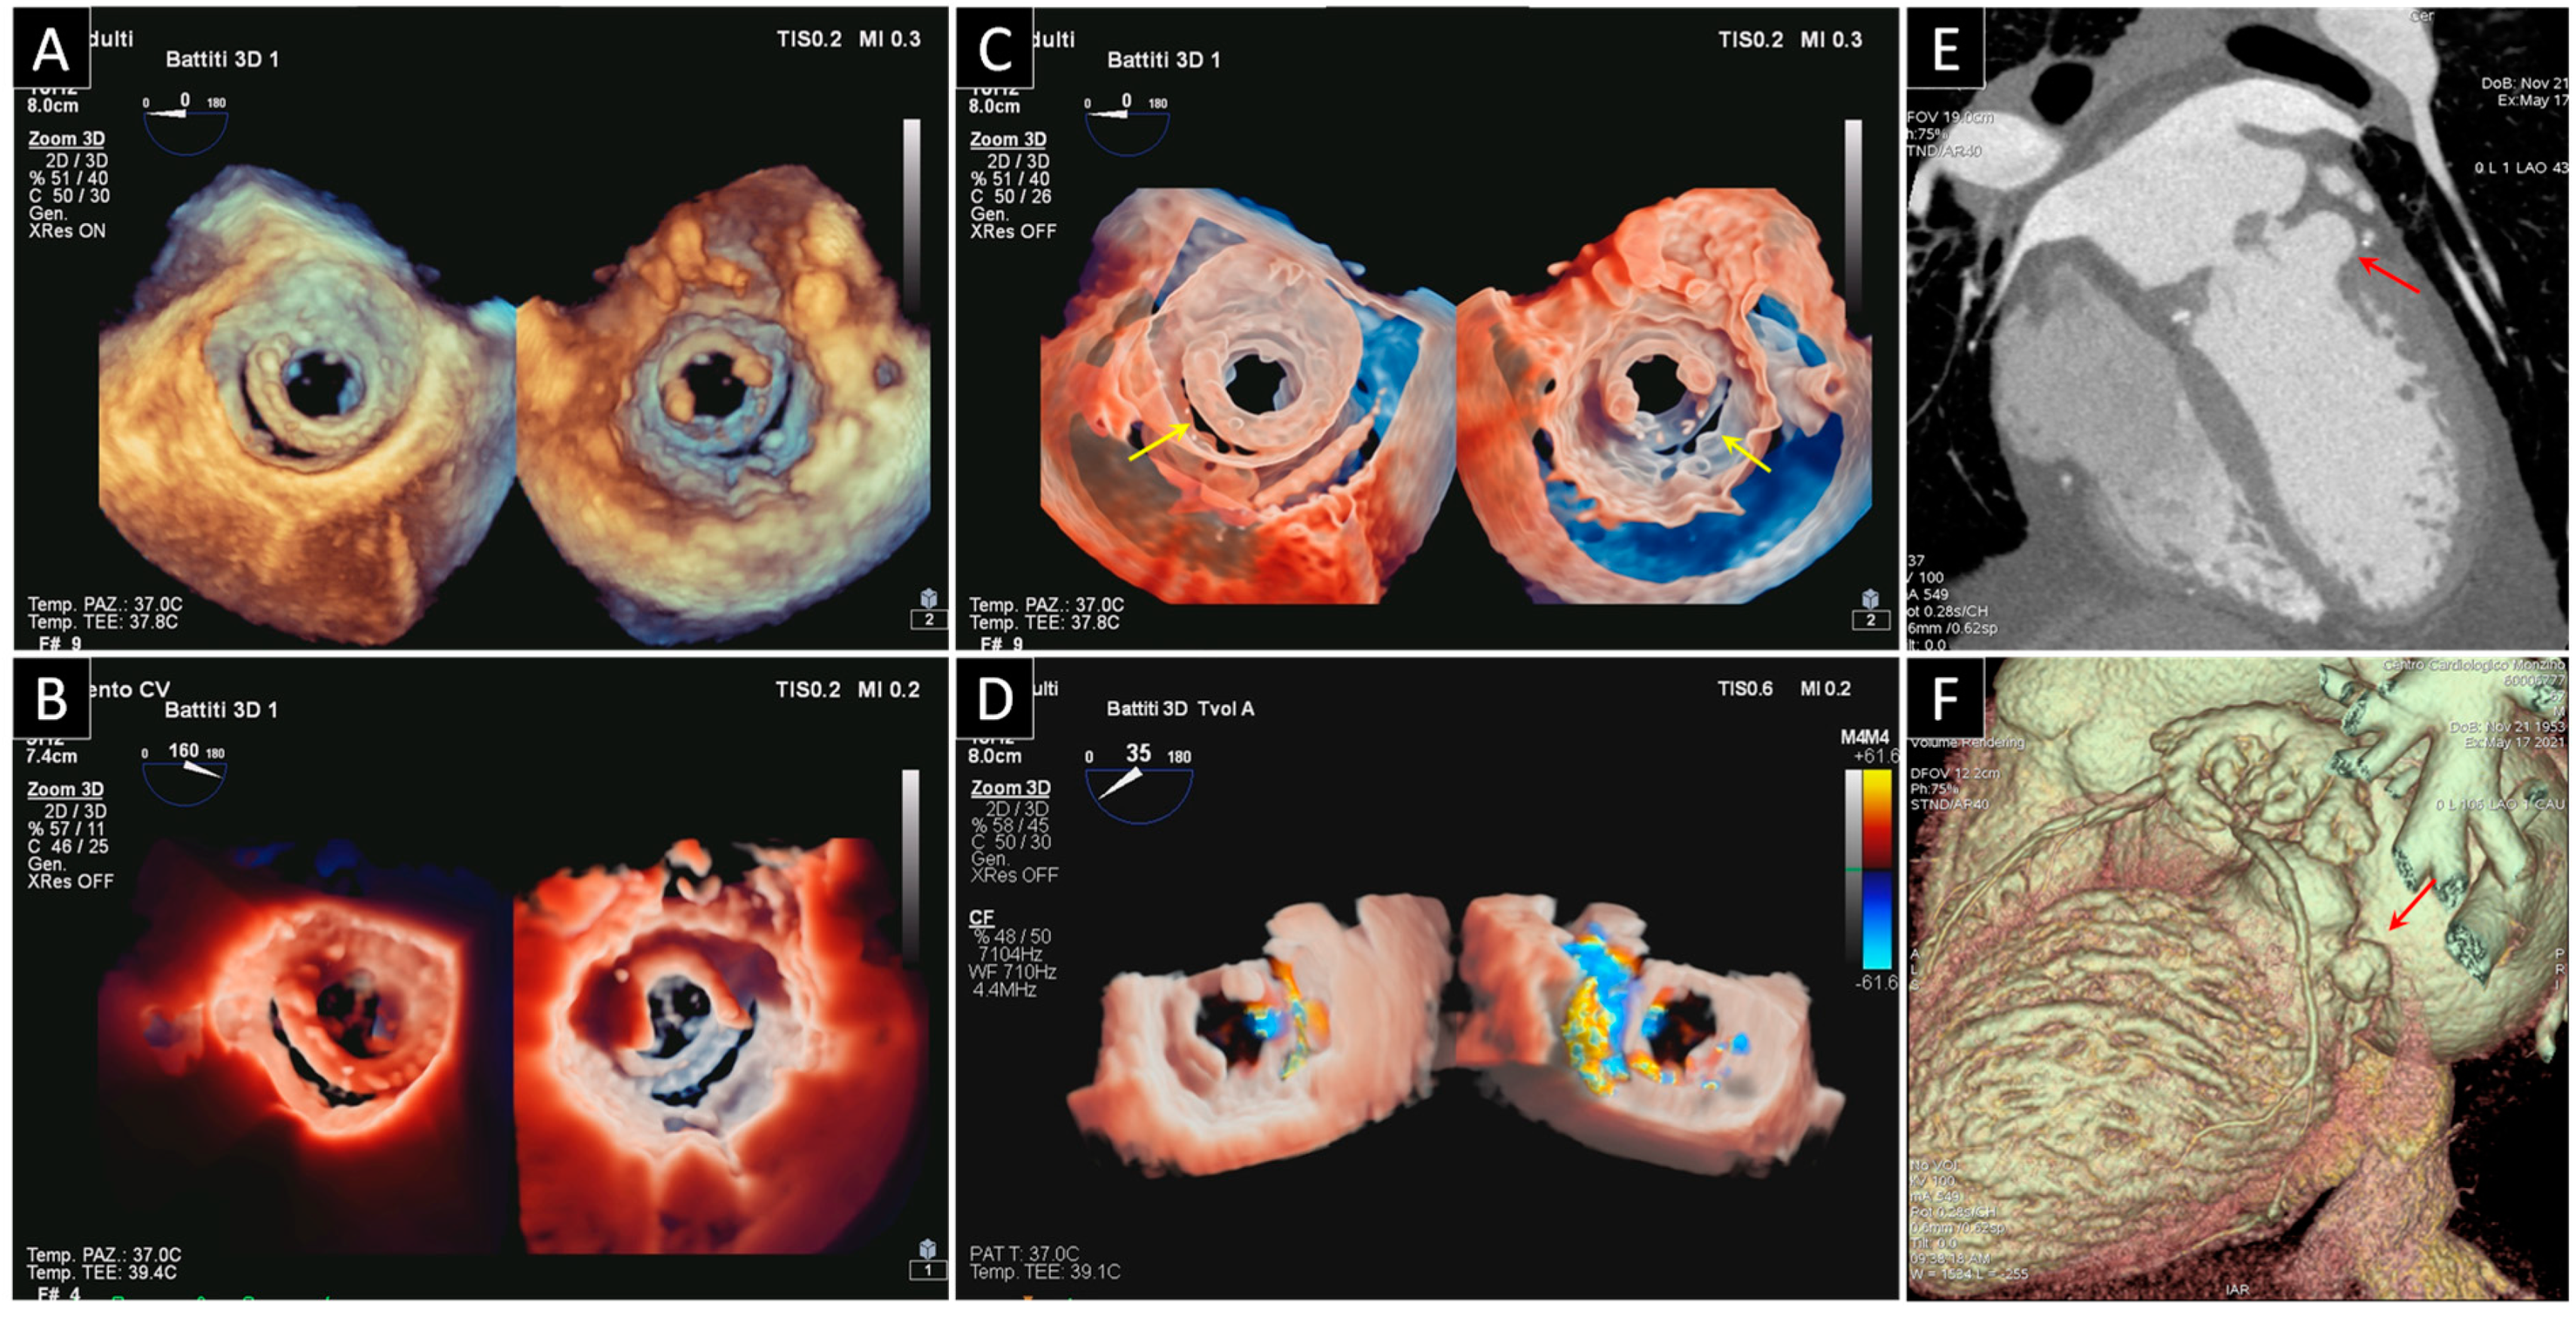

4. Bioprosthetic Structural Valve Degeneration

4.1. Mitral Bioprosthetic SVD

4.2. Aortic Bioprosthetic SVD